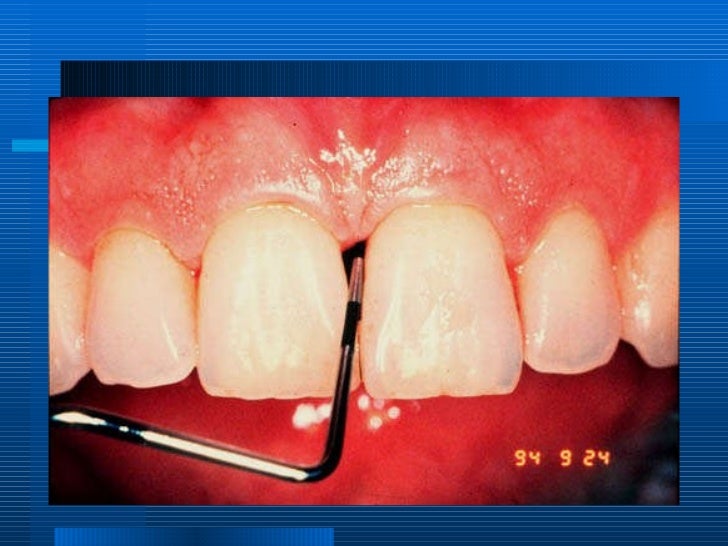

periodontitis associated with endodontic lesions